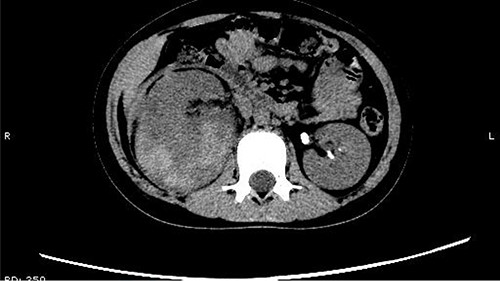

On 25 February, the patient complained of left back pain, nausea and vomiting. A further CT scan showed some irregular high-density shadows persisted in the left renal pelvis (Fig. 3) and an irregular high-density shadow was present in the left upper ureter (Fig. 4); furthermore, hydronephrosis was apparent in the left renal pelvis. There were no abnormalities in the bladder.

Some irregular high-density shadows persisted in the left renal pelvis, hydronephrosis was apparent in the left renal pelvis.